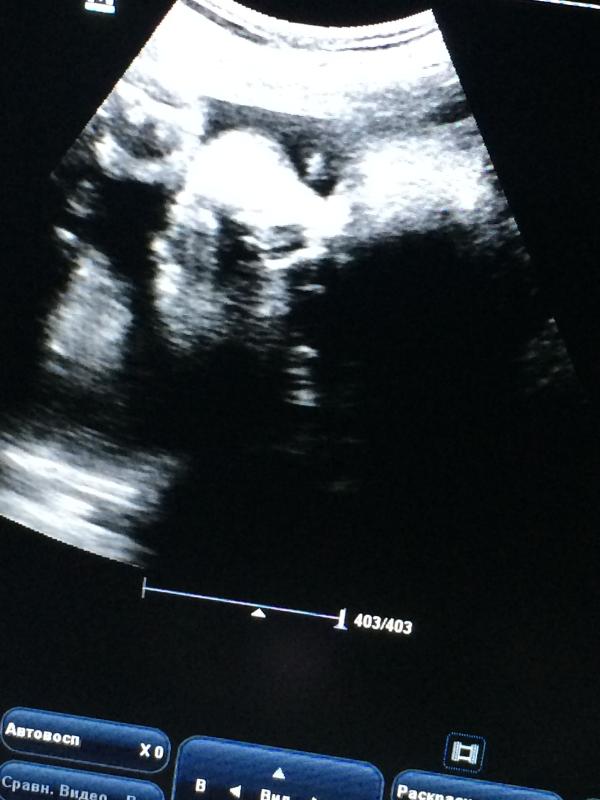

Мой губастик весит 2 кг😍 а вы найдёте его лицо ?🙉нужно перевёрнут экран чтоб увидит 😃

Ну ты мать, его откормила😂 к кому ходила на узи?

😂все равно не вижу